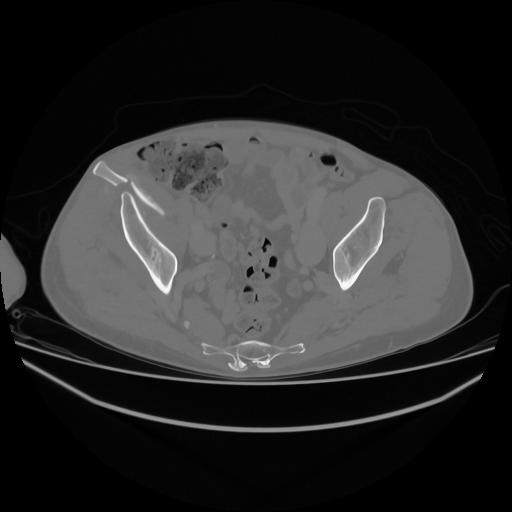

5 CUERPO,CE,Vol,1.0,CUERPO,,